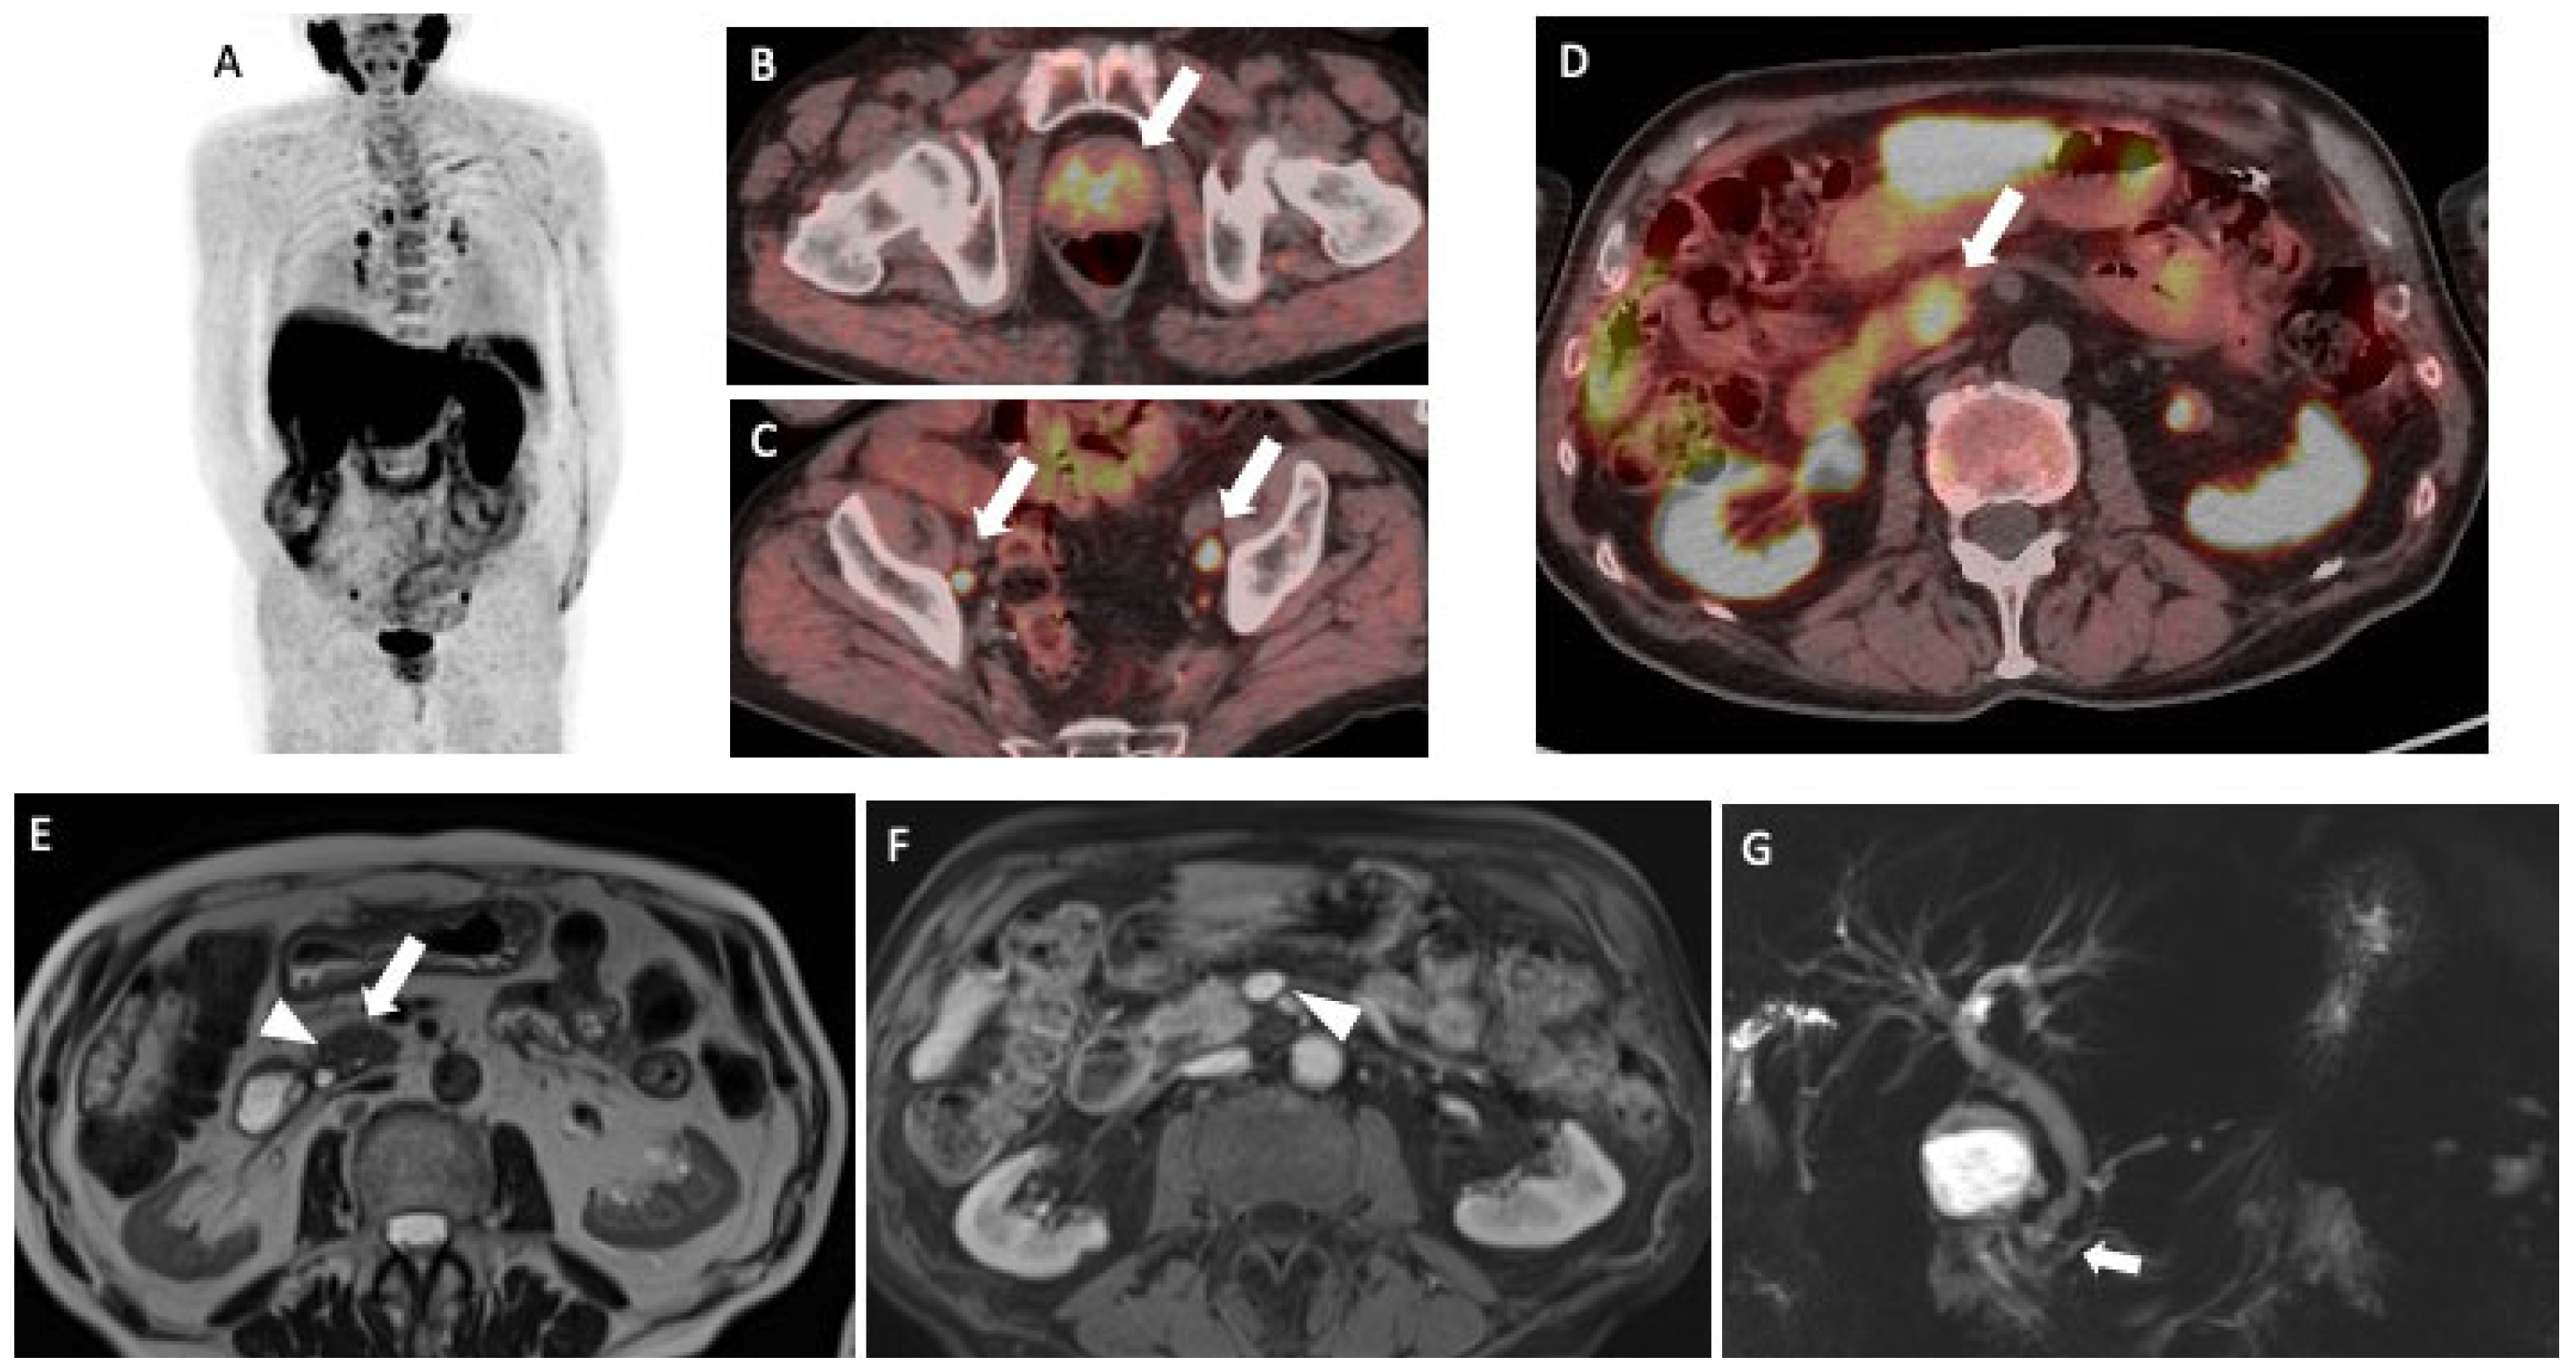

An Incidental Pancreatic Finding at 18F-Choline PET/CT: Chronic Mass-Forming Pancreatitis